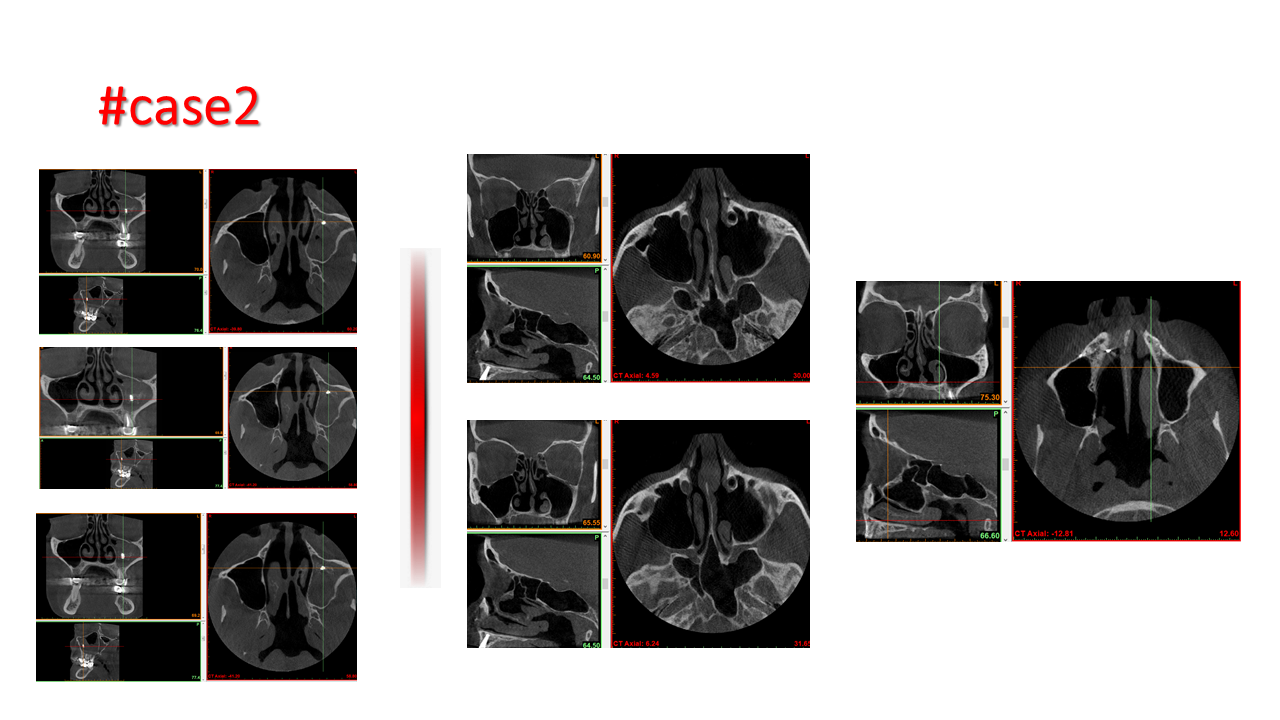

FESS Case Review and Radiologic Analysis (30.09.2016)

Case-based presentation focused on pre- and postoperative imaging in functional endoscopic sinus surgery (FESS). Includes anatomical landmarks, surgical variations, sinus pathology, and technique evaluation. Delivered by Dr. Levon Galstyan at AAOMFS.